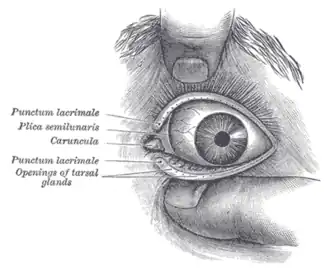

Humans have two eyes, situated on the left and the right of the face. The eyes sit in bony cavities called the orbits, in the skull. There are six extraocular muscles that control eye movements. The front visible part of the eye is made up of the whitish sclera, a coloured iris, and the pupil. A thin layer called the conjunctiva sits on top of this. The front part is also called the anterior segment of the eye.

There are two major measures of eye irritation. One is blink frequency, which can be observed by human behavior. The other measures are break up time, tear flow, hyperemia (redness, swelling), tear fluid cytology, and epithelial damage (vital stains) etc., which are human beings' physiological reactions. Blink frequency is defined as the number of blinks per minute and it is associated with eye irritation. Blink frequencies are individual with mean frequencies of < 2–3 to 20–30 blinks/minute, and they depend on environmental factors including the use of contact lenses. Dehydration, mental activities, work conditions, room temperature, relative humidity, and illumination all influence blink frequency. Break-up time (BUT) is another major measure of eye irritation and tear film stability.[74] It is defined as the time interval (in seconds) between blinking and rupture. BUT is considered to reflect the stability of the tear film as well. In normal persons, the break-up time exceeds the interval between blinks, and, therefore, the tear film is maintained.[63] Studies have shown that blink frequency is correlated negatively with break-up time. This phenomenon indicates that perceived eye irritation is associated with an increase in blink frequency since the cornea and conjunctiva both have sensitive nerve endings that belong to the first trigeminal branch.[75][76] Other evaluating methods, such as hyperemia, cytology etc. have increasingly been used to assess eye irritation.